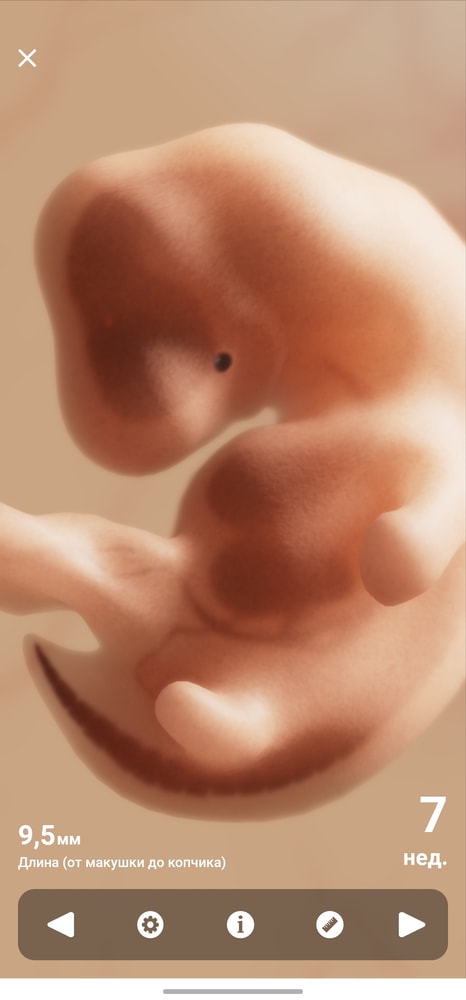

Ну, человеческий эмбрион в 7 недель развития и выглядит как гусеница))

Вот мой в 7 недель 2 дня, с КТР 10.7. Просто капля😂 Все у вас отлично, подождите недельку-две, уже будет шарик с ножками и ручками. ЧСС у вас нормальный, не низкий и не высокий, все как надо